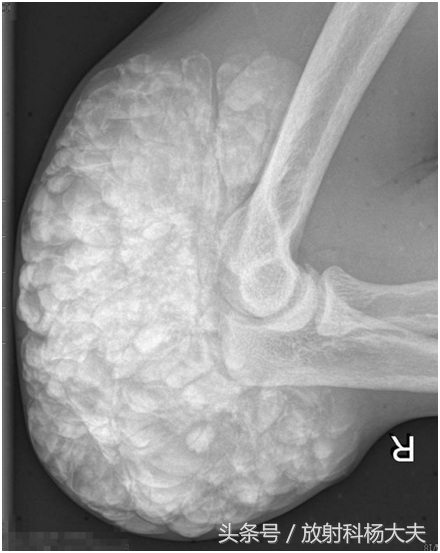

刘叔今年50岁,刘叔是赫赫有名的农村致富能手。12年前发现右侧肘部及前臂皮下多个质软结节,无明显红热痒痛现象,肘关节活动正常,随时间推移,上述结节逐渐增大,后沿尺骨方向逐渐形成成块并影响肘关节活动。刘叔半个月前来我院就诊。骨科专科检查:包块长度约10cm,宽度5.5cm,触之硬韧,边界不清,并轻微压痛。x线片:右肘关节各构成骨未见增生、破坏等骨质异常X线征,右肘关节旁软组织中可见团状阴影,团块由大量大小不一结节状高密影融合而成的。

在骨关节的X线片上,通常在骨骼或骨骼边上看到这种高密度的类似骨骼一样东西,我们会考虑哪些?骨肉瘤,软骨肉瘤,创伤性骨炎,还有某些疾病引起的钙化,骨化等等。

一周前,刘叔通过手术把肿物切除了,肿物也送去病理检验。病理报告示:致密的纤维结缔组织中可见大量钙盐沉积,周边可见异物巨细胞反应的肌纤维母细胞增生,符合软组织肿瘤样钙化。临床诊断:肿瘤样钙质沉着症。

X线检查是诊断TC的基本方法, 其表现为关节旁关节伸侧软组织中, 呈大小不一的钙化结节集结而成的分叶状团块,呈“卵石样”,“桑葚状”,范围较广者可呈“流注状”;病变一般不累及邻近关节或骨骼。CT与X线平片表现一致,但CT对病变部位、形态及范围的显示更为全面, 能清楚显示病变与邻近关节及骨骼的关系。MRI具有多参数、多序列、多方位成像的功能,可根据信号判断组织成分,。能多方位显示病变不累及关节或骨骼, 对诊断有较大帮助。